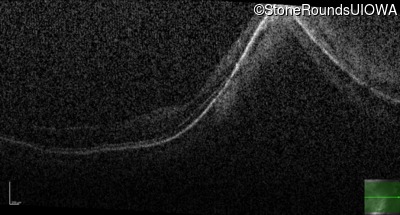

Optical Coherence Tomography - Right - 20/30 +2

Exemplar / OCT Stack